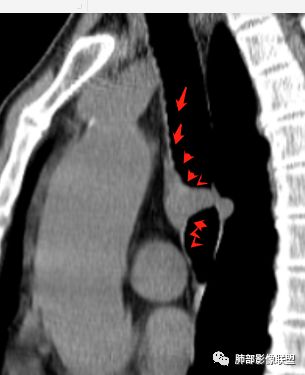

南边分析:针对本例,病灶跨气管壁内外生长,常规跨内外的有:恶性肿瘤为主,其次就是神经源性、平滑肌瘤;常规的思维:跨内外就要看结构的变化气管的优势在于软骨相对密度高,而且成C型

我们如何分析这个病例?冠状位:软骨密度稍高;病灶区软骨部分区域不连续,外围连续,提示病灶推移为主,不是破坏为主;如果破坏,应该这些软骨显示不清,移位不明显

病灶从软骨见推移开,跨内外,因此定在良性。恶性是侵犯,破坏为主,如果破坏,应该这些软骨显示不清,移位不明显,不是推移为主这例病变定在良性,我们就要考虑:1、软骨之间的平滑肌来源;2、神经源性

南边:

南边:高密度软骨在这两点上停了

南边:挤过去了,说明是从软骨间过去的

杨泽锋:明白了,推移是本质、跨是现象,要向南大学习透过现象看本质的能力

尘缘:@Shelia,部分是向前推,部分是向后推的。这个地方应该还有向后推的;肿物是从向前推与向后推这个间隙跨软骨的。

南边:需要用连续的窄窗观察。

病例小结      气管神经鞘瘤属于罕见的气管良性肿瘤,一般气管良性肿瘤或腔内或腔外生长的结节样改变,恶性肿瘤呈腔内外生长,但本例肿块向腔外生长,呈“冰山样改变”,即肿瘤的腔内部分较小而腔外部分较大,无周围组织侵犯。因此肿瘤腔内外生成不能作为鉴别气管良恶性肿块的绝对依据。        因此冠(矢)状位多平面观察、软骨是否破坏、气管壁有无增厚等细节观察,对于鉴别气管肿块良恶性有重要的参考性。